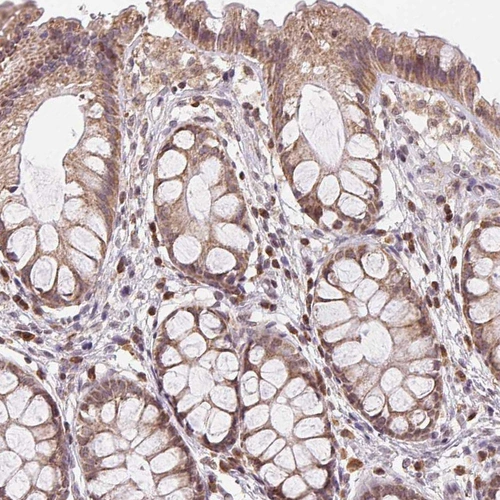

Immunohistochemistry analysis in human testis and skeletal muscle tissues using HPA057508 antibody. Corresponding PIWIL4 RNA-seq data are presented for the same tissues.